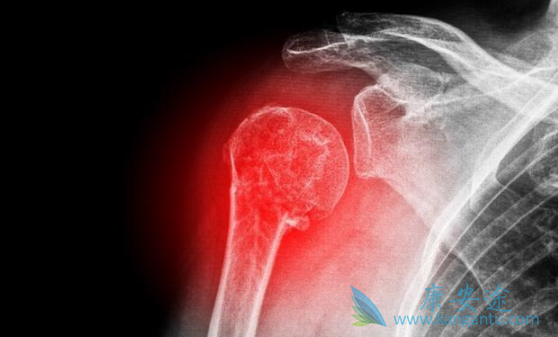

尤文氏肉瘤和骨肉瘤是儿童和青年人最常见的骨原发恶性肿瘤。具有恶性程度高、易转移、预后差等特点。受限于治疗手段,骨肉瘤标准治疗以大剂量的化疗以及手术治疗广泛的切除肿瘤为主,而尤文氏肉瘤主要以放疗联合化疗为主,暂时无靶向药可用。2018年ESMO会议上公布的最新研究显示:多靶点抑制剂卡博替尼(Cometriq)对尤文氏肉瘤和骨肉瘤具有很强的抗肿瘤活性,为这两种骨原发恶性肿瘤提供了治疗新选择。

一项各入组45名的12岁以上不能切除的局部晚期或转移性尤文氏肉瘤和骨肉瘤患者的单臂Ⅱ期临床试验,患者接受每天一次、每次60mg的卡博替尼口服治疗,每8周进行影像学肿瘤评估。数据显示:骨肉瘤组最终有42例患者的疗效可评估:5例(11.2%)用药后出现进展,8例(19%)病灶达到局部缓解,22例(52%)肿瘤负荷降低。骨肉瘤卡博替尼治疗组患者中位无疾病进展生存期(PFS)为6.2个月;骨肉瘤卡博替尼治疗组总生存期(OS)为10.6个月。

尤文氏肉瘤患者中,最终可评价疗效的共32例,其中4例(12.9%)进展,9例(28.1%)达到局部缓解,22例(71%)肿瘤负荷降低。尤文氏肉瘤卡博替尼(Cometriq)治疗组中位无疾病进展生存时间(PFS)是5.2个月,尤文氏肉瘤卡博替尼治疗组总生存期(OS)是9.8个月。在这项对晚期或转移性骨肉瘤和尤文氏肉瘤肉瘤靶向治疗的Ⅱ期单臂研究中,卡博替尼表现出了迄今为止最高的抗肿瘤活性。